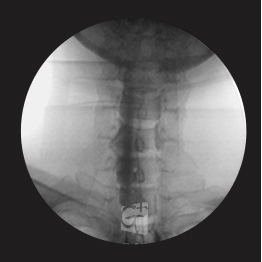

요추 선택적 신경치료

요추 5번에서 시행된 선택적 신경치료 약물이 신경근과 추가공 안쪽으로 잘 퍼지는 모습